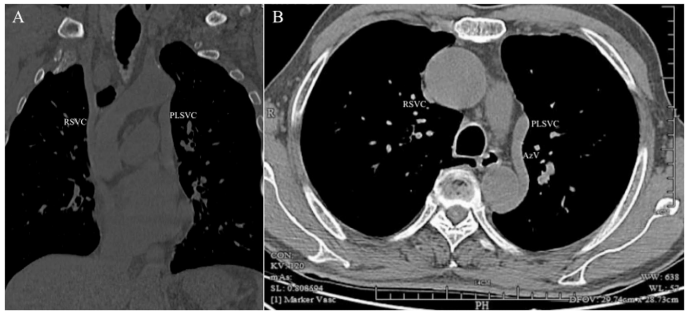

《BMC Surgery》最新发表的这项研究通过一例典型病例填补了这一空白。Li Zhang和Jingjin Wu*团队报道了73岁男性直肠癌(T4aN1bMx)患者术后化疗时,意外发现Ⅲb型PLSVC合并左侧奇静脉引流变异。术前CT三维重建显示右奇静脉缺如,左侧奇静脉汇入直径达9.8mm的PLSVC(较右侧SVC的3.3mm更粗)。通过左腋静脉(AxV)入路,术中使用血管造影确认解剖结构后,将导管尖端置于PLSVC远端,导管-静脉比仅18%,远低于45%的血栓风险阈值。

影像学发现:CT冠状位显示左奇静脉沿降主动脉左侧上行,轴位证实其汇入PLSVC的独特走行。